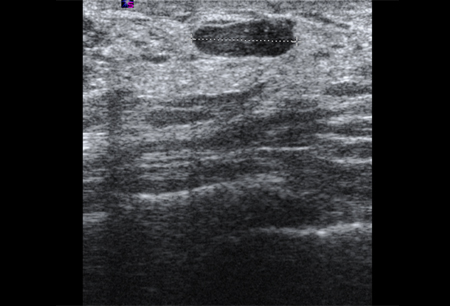

Imagem ultrassonográfica do espessamento da pele em paciente com câncer de mama inflamatório

Cortesia da Dra. Nancy Pile, Universidade de Louisville; usado com permissão